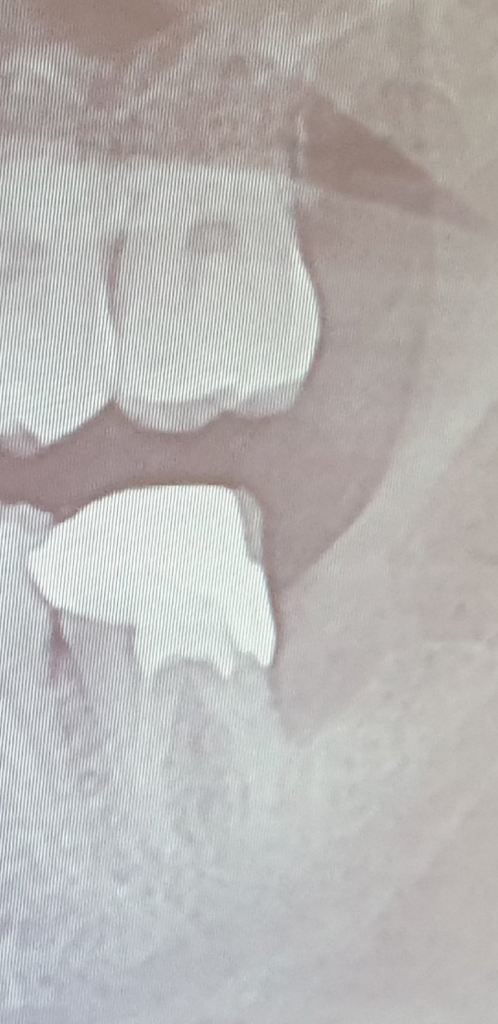

• 2번 째 사진

회복될 수 있을 것으로 보여집니다. 사랑니로 인하여 어금니가 손상되고 뒤쪽 염증이 심해진 상태기 때문에 발치 이후 흔들림이 나타날 수 있습니다. 다만 단기간은 아닐 것으로 보이며 뼈가 차오르는 것을 추적 관찰 해보아야 할 듯 합니다. 뼈가 정상적으로 잘 차오른다면 흔들림이 잡힐 것으로 보입니다. 지금으로서는 구강 위생 관리를 잘해주는 방법 밖에 없습니다.

어느정도는 치조골이 회복되겟지만 완전히는 회복되지 않습니다. 뒤쪽으로 치조골이 많이 흡수되엇으니 양치를 하실때 꼼꼼히 해주시고, 정기적으로 치과를 다니시면서 잇몸관리를 받으셔야될것같습니다.

뼈가 많이 녹아서 다시 차오르기는 힘들 것 같습니다